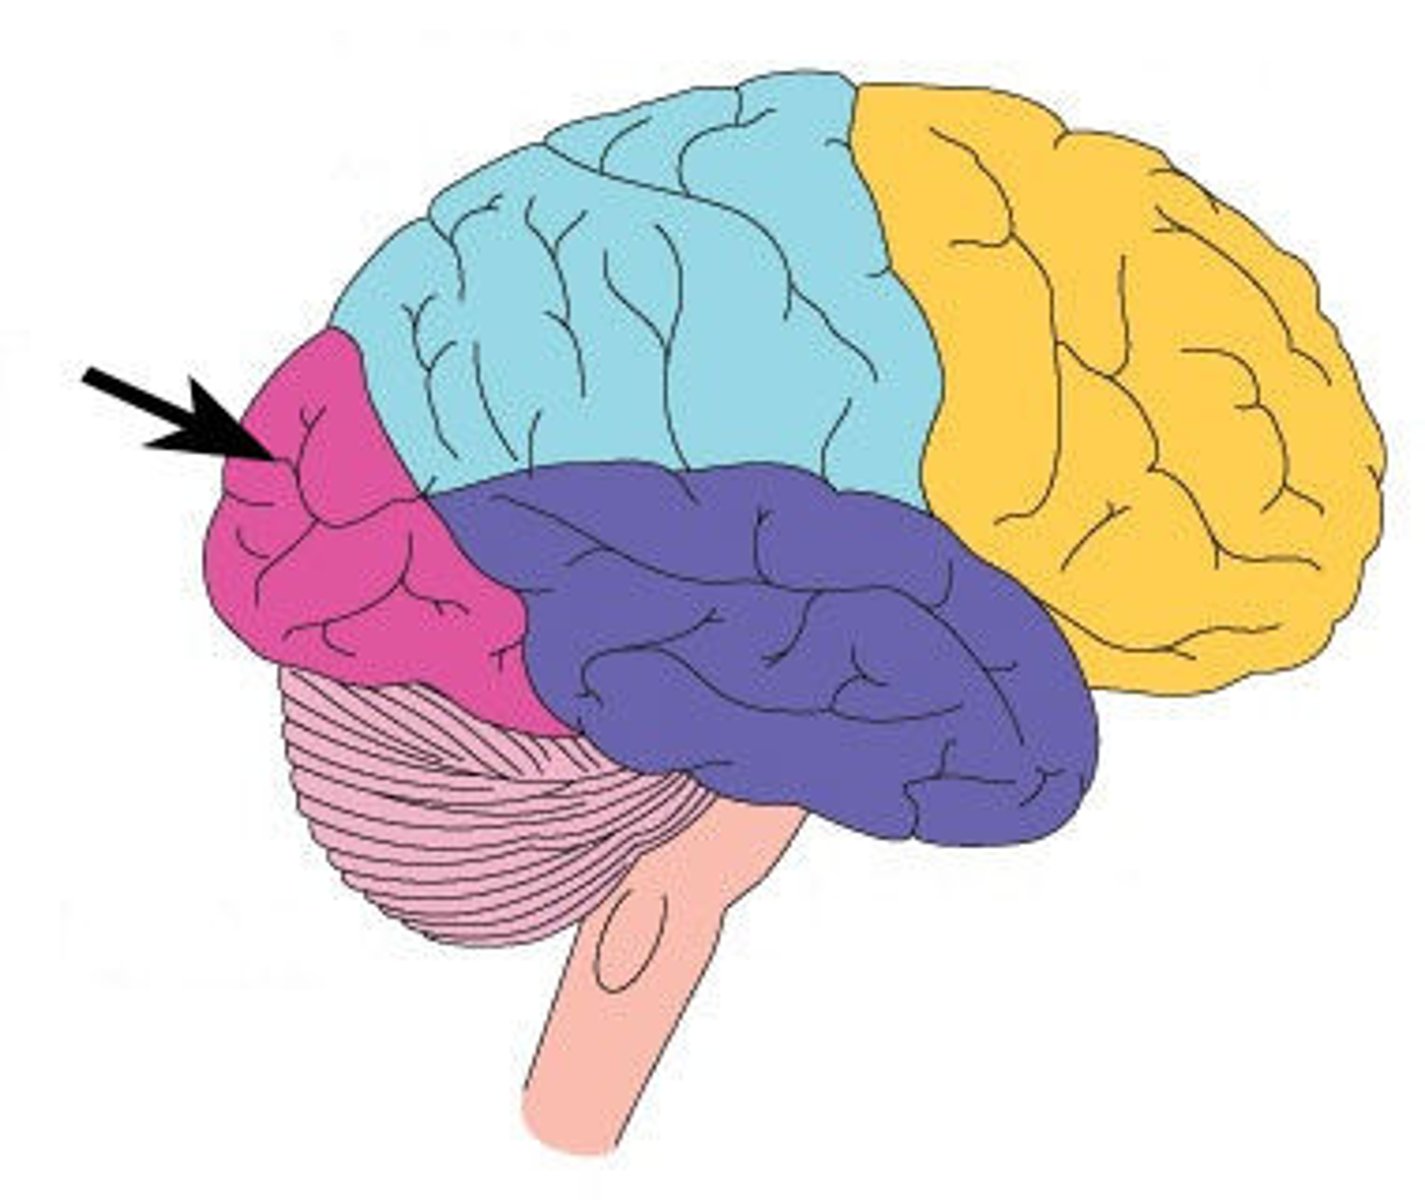

Surface lobes of the cerebrum

Frontal Lobe,

Temporal Lobe,

Parietal Lobe,

Occipital Lobe

Frontal Lobe

Primary (somatic) motor cortex

Frontal lobe: motor cortex

1) Controls precise or skilled voluntary movements of our skeletal muscles

2) Also learned motor skills (repititious or patterned nature) like playing an instrument or typing

3) Is contralateral: left primary motor cortex controls muscles on right side of body & vice versa

Clinical: damage to frontal lobe

Damage to localized areas of frontal lobe (such as from a stroke) paralyzes body muscles controlled by those areas.

Only voluntary control is lost, however, as muscles can still contract reflexively.